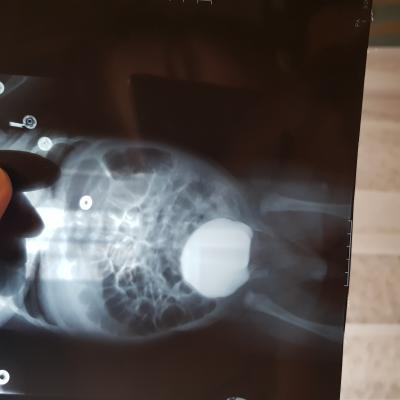

Болезнь Ормонда (ретроперитонеальный фиброз, забрюшинный фиброз) – хроническое воспаление жировой клетчатки забрюшинного пространства, которое постепенно приводит к компрессии и нарушению проходимости трубчатых структур данного анатомического участка. Чаще всего, в качестве этих тубулярных структур выступают мочеточники.

У меня есть сомнения, что причиной гидронефроза в Вашем случае явилось именно это состояние.

Возможно речь идет о пузырно-мочеточниковом рефлюксе.